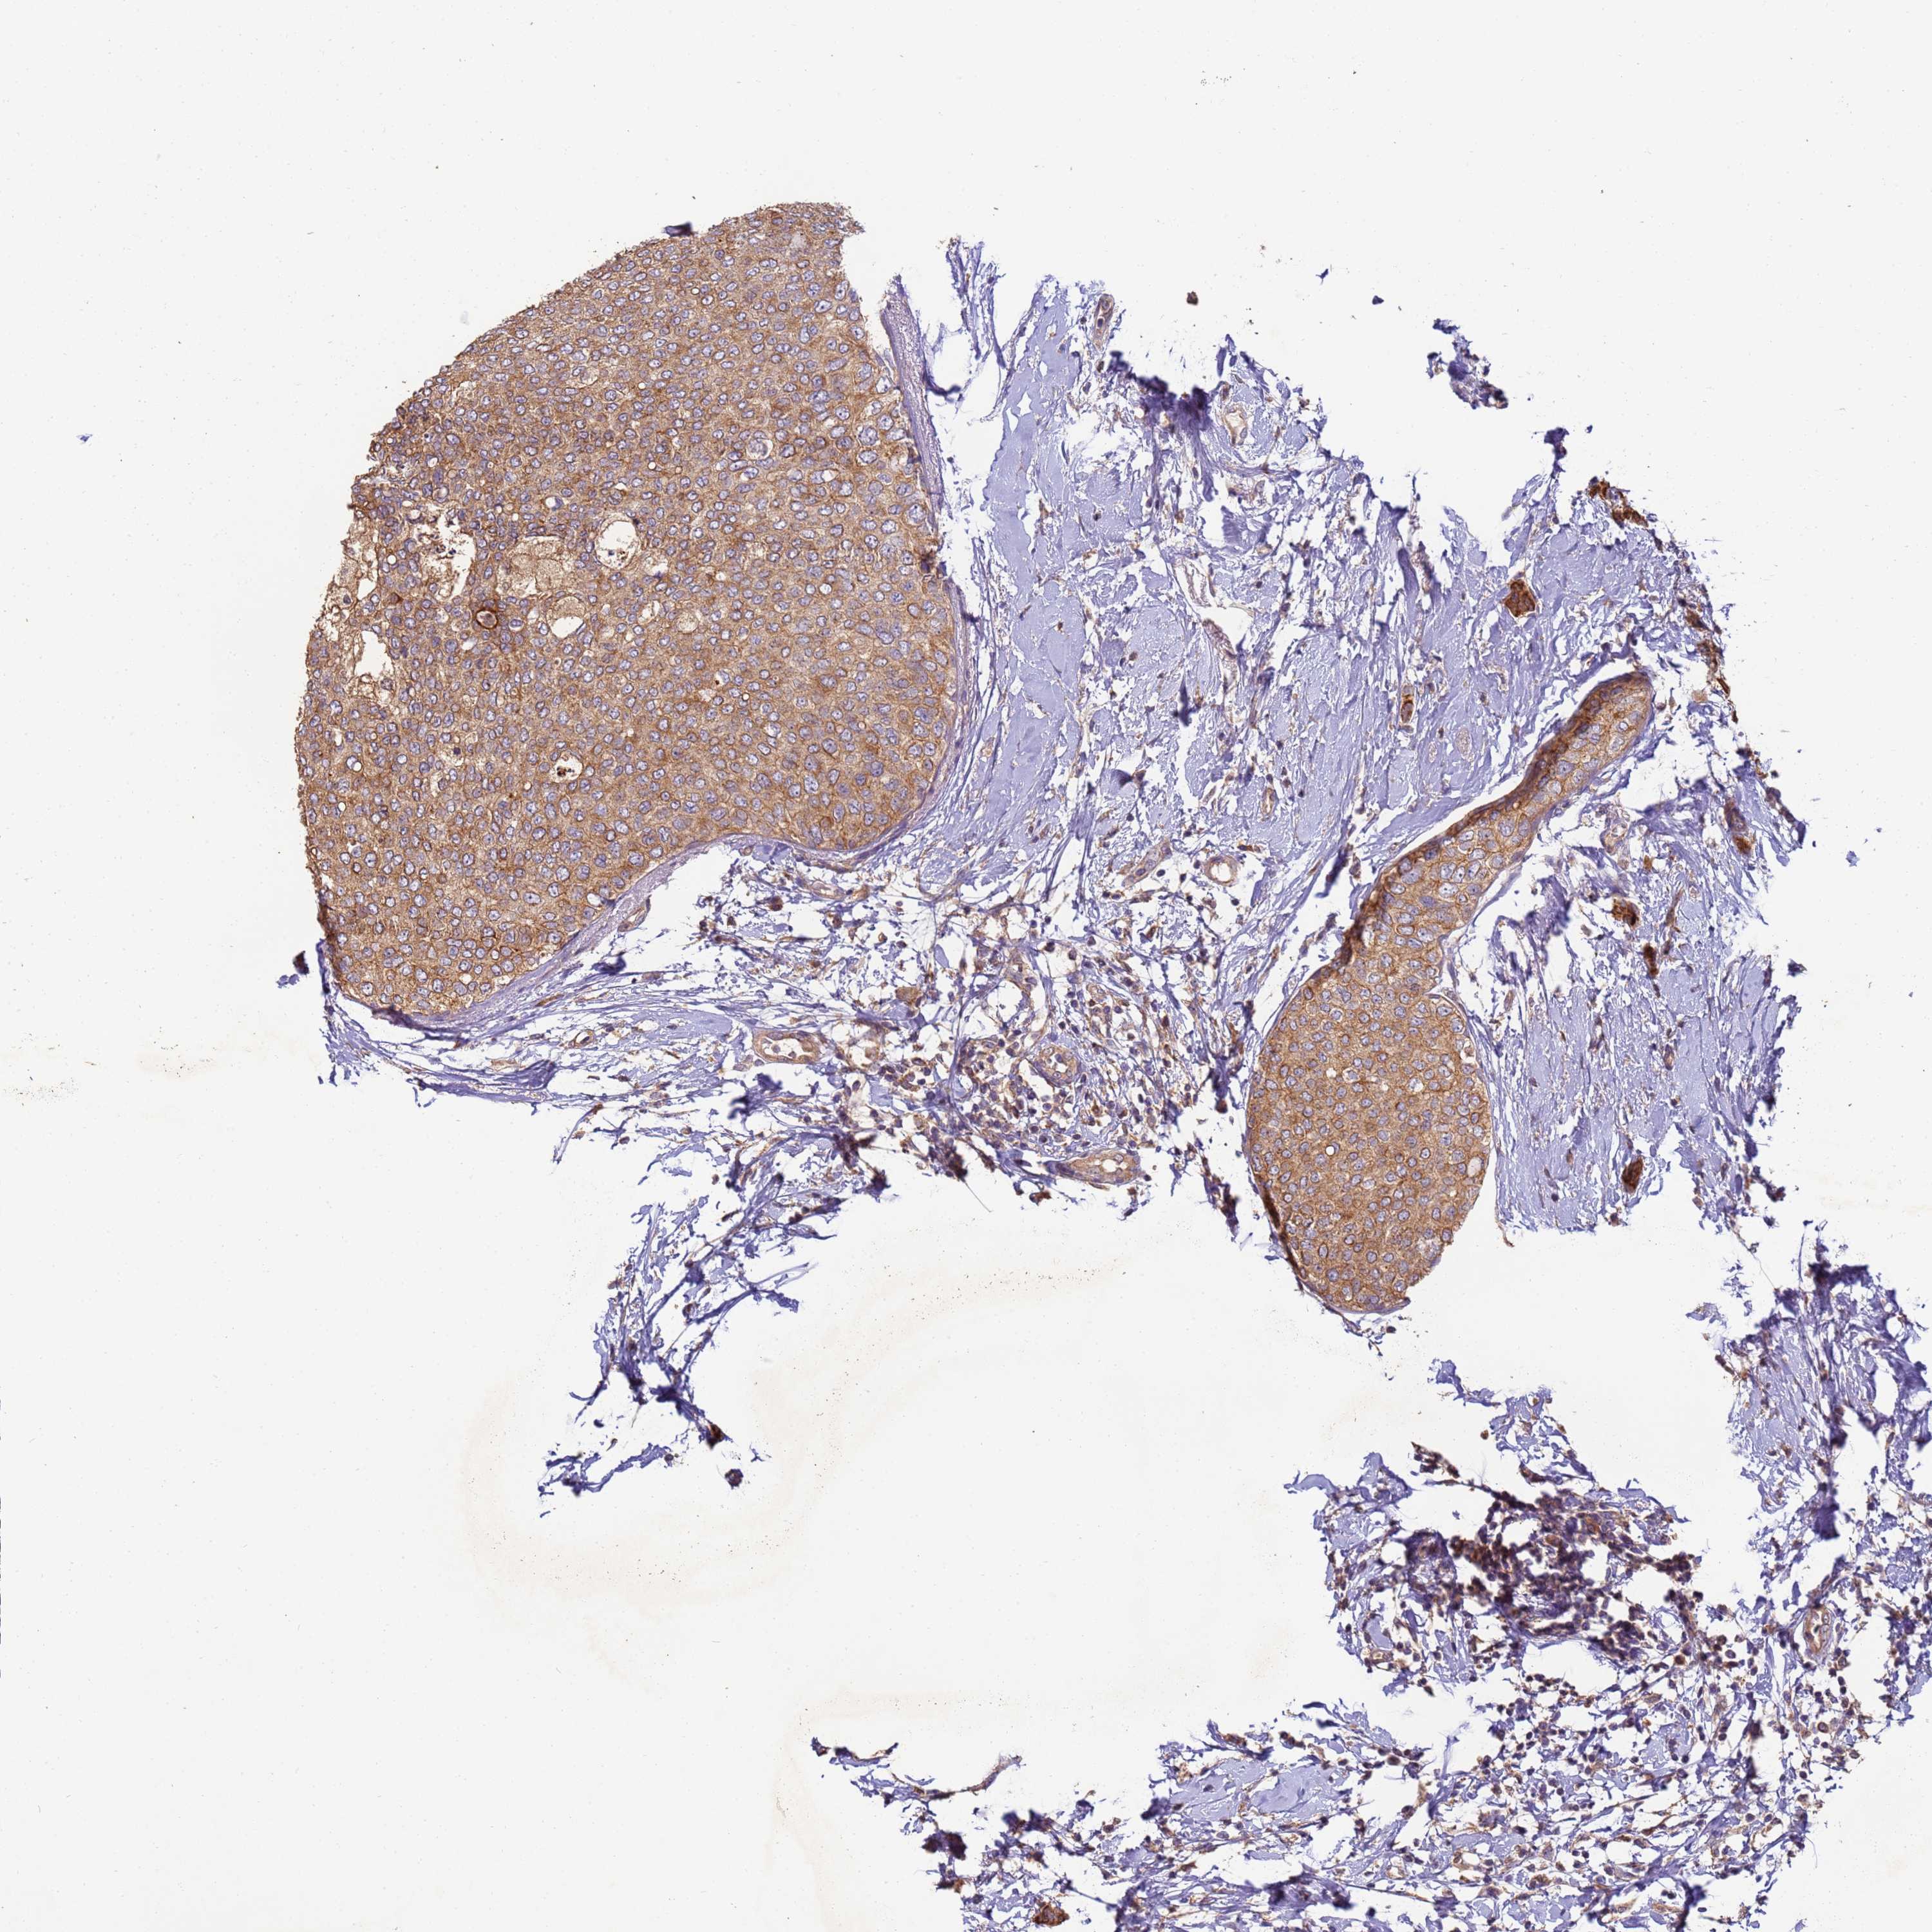

CANCER BREAST CANCER Show tissue menu

BRCA TCGA BRCA VALIDATION PROTEIN EXPRESSION